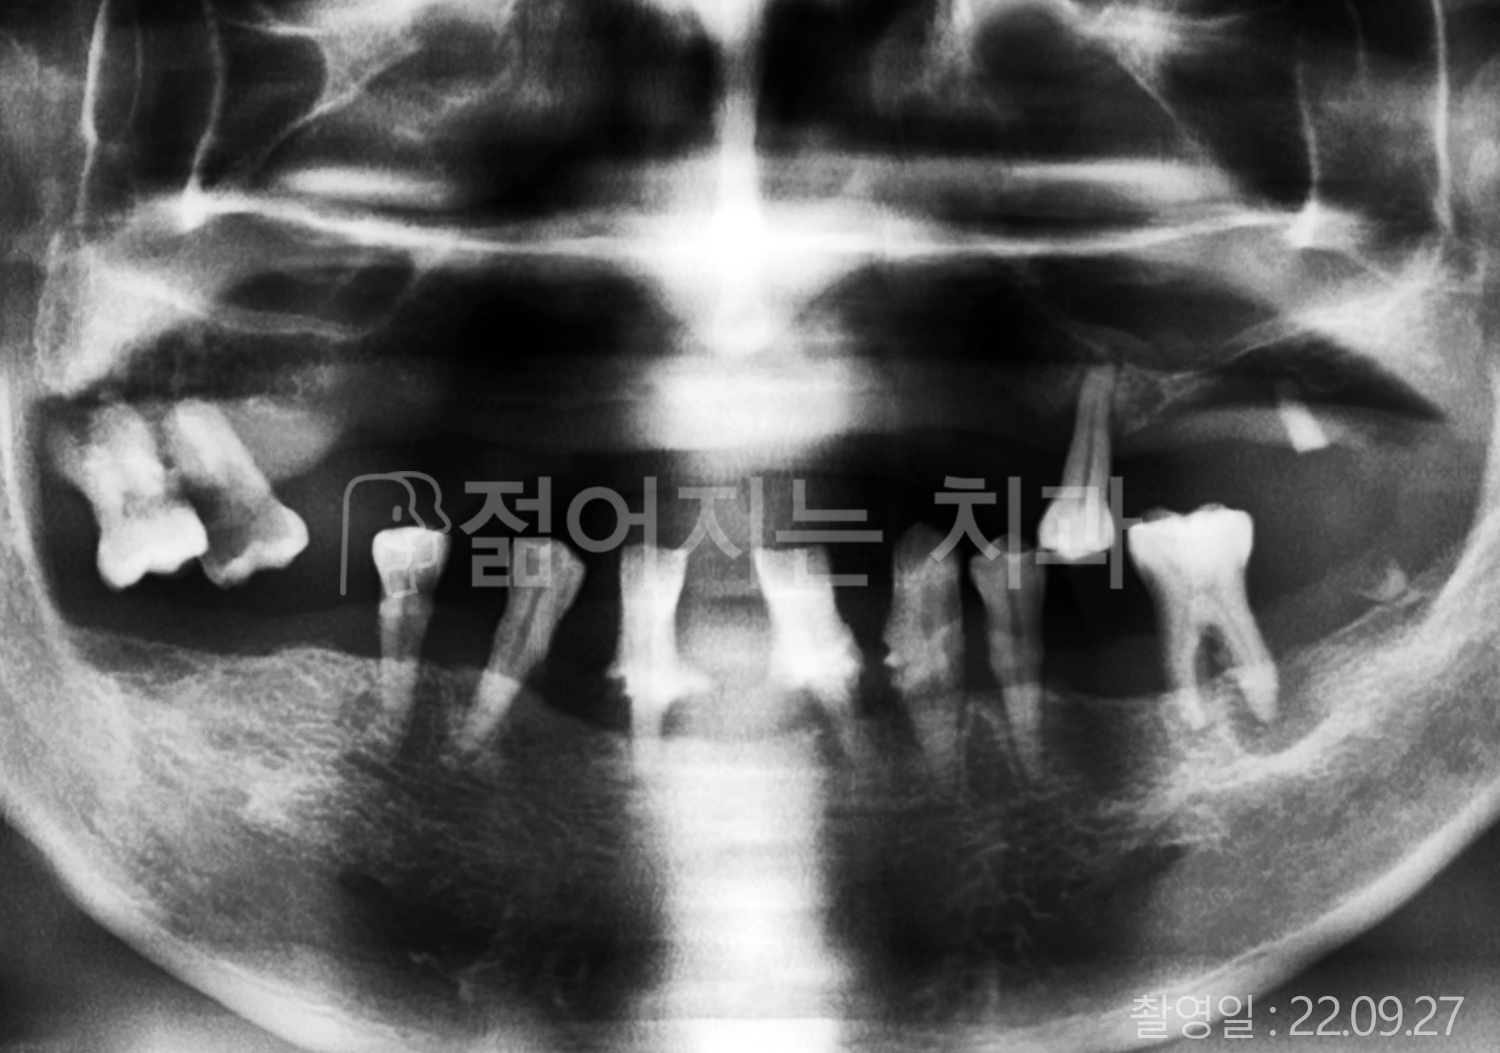

• 40대 전체치아 10개 이상 임플란트

• 50대 전체치아 10개 이상 임플란트

• 50대 고혈압, 당뇨, 고지혈증 전체치아 10개 이상 임플란트